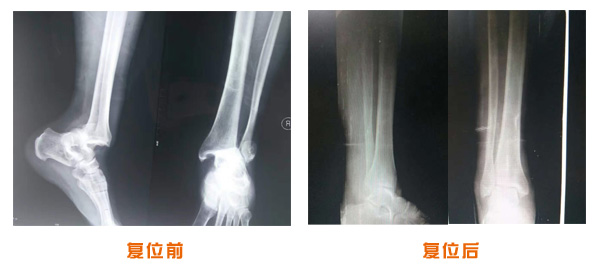

肥城市安駕莊梁氏骨科醫(yī)院是一所以梁氏手法正骨配合膏藥為特色的現(xiàn)代化??漆t(yī)院。

梁氏骨科術(shù)始創(chuàng)于清雍正年間,歷經(jīng)八代,至今已有三百年歷史。據(jù)1929年泰安縣志載“梁瑞圖先生,字增生,號(hào)蓮峰,安駕莊人,精岐黃并發(fā)明接骨,凡跌打車凡跌打車軋皮不破而碎骨者......【詳細(xì)】 |